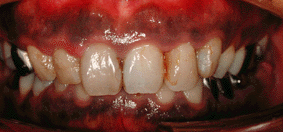

3.歯周病 歯周組織への影響 ・歯やその周囲に汚れがたまりやすくなる たばこの煙の中のタールは、俗に言うヤニとして歯の表面にこびりつきます。この部分には歯垢(プラーク)も沈着しやすくなり歯周病の発症や進行を助けます。 ・細菌に対する組織の抵抗力をが低下する ニコチンが歯肉や口腔粘膜からも吸収され、その付近の白血球などの免疫担当細胞の働きを鈍らせるため、細菌が体内に簡単に侵入して毒素などによる周りの組織の破壊を始めます.。そのため歯周病が発症したり、悪化し易くなります。 ・傷や治療を受けたところの治癒が悪くなる ニコチンにより、傷口をふさぐ細胞の動きが鈍くなりせっかく歯の治療を受けても良い結果が得られません。 | |

| たばこで歯が悪くなり、虫歯や入れ歯が多くなる | |

| 写真2 60代男性 喫煙歴40年 | 写真3 60代男性 喫煙歴30年 |